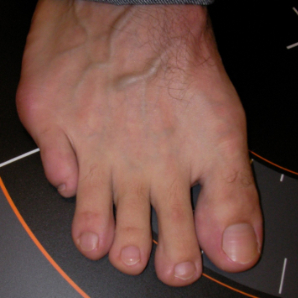

Hallux Valgus (juanete)

Hallux valgus: antes Hallux valgus: después